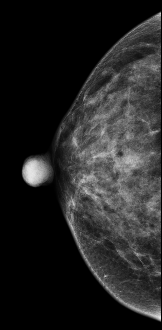

CESM图像:

常规检查:右乳偏外下象限见模糊类圆形结节影,CESM显示结节不均匀强化

右乳偏外下限结节,考虑恶性,建议活检后手术切除。

术后病理证实:浸润性导管癌